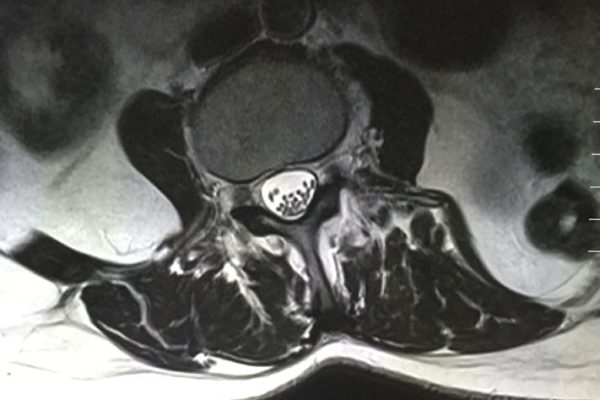

Il macchinario in dotazione presso il nostro Centro è una Risonanza Magnetica completamente aperta costituita da un magnete potente ma compatto a forma di G che fornisce un facile accesso al paziente ed un semplice posizionamento su un tavolo rotante, ampio, stabile e confortevole; si tratta infatti di un'evoluzione moderna della risonanza, nata per soddisfare le esigenze dei pazienti, in particolar modo di quelli che soffrono di claustrofobia e di tutte quelle persone che hanno difficoltà nel sottoporsi alla risonanza magnetica classica eseguita all'interno di una struttura cilindrica dallo spazio ridotto. Tali caratteristiche la rendono un’apparecchiatura ottimale nello studio dell'intera colonna vertebrale e delle articolazioni, permettendo un’ottima visualizzazione delle strutture ossee, cartilaginee, muscolari, tendinee e legamentose.